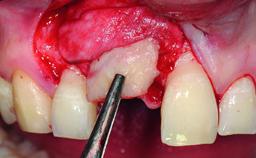

Replacement of a Missing Upper Left Central Incisor, Late Placement of an RC Bone Level Implant and Adjacent Tooth Restoration

A healthy 38-year-old male patient was referred for replacement of a failing tooth-supported cantilever fixed dental prosthesis on teeth 11 and 21. The patient reported a history of trauma at 13 years of age that had resulted in the subsequent loss of tooth 11, as well as endodontic treatment of the adjacent abutment tooth 21. A metal-ceramic cantilever fixed dental prosthesis replacing tooth 11 had been provided by his general dentist several years after the loss of the tooth, with tooth 21 as the sole abutment. At the time of initial presentation, this restoration had been in service for over 20 years.

Bone Volume | Deficient horizontally, allowing simultaneous augumentation |